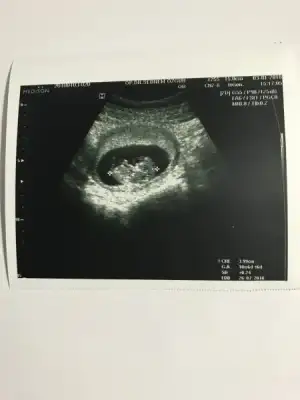

Bende pko var Cnm altı ay dur istiyorduk ovulasyon testiyle takip ettim günümü yumurtlama gününden bi gün önce ve sonra ilişki oldu öncesinde beş gün olmadı eşim yoktu ama ben le onla alakası yok tamamen nasip Cnm